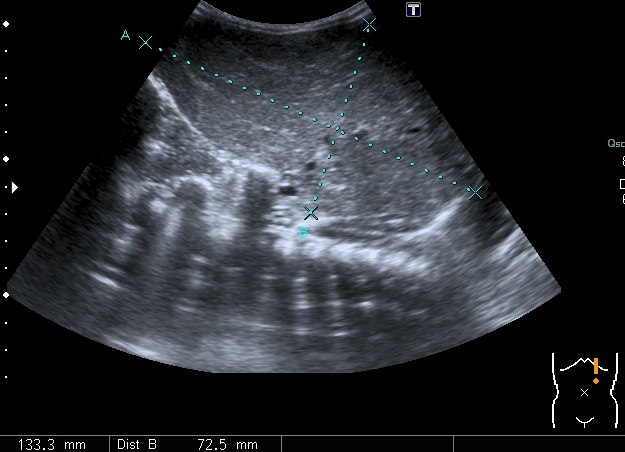

Правый надпочечник представлен округлым гиперэхогенным тканевым образованием с участками кальцификации, гиповаскулярным по отношению к ткани печени и почки

Моё заключение: нейробластома правого надпочечника с тотальным метастатическим поражением печени. Прошу членов форума высказать своё мнение о случае. Постараюсь отследить верификацию.

Верифицированный морфологически диагноз: С74.9 Низкодифференцированная нейробластома правого надпочечника с метастатическим поражением печени и костного мозга. T2N0M1, IVS стадия.